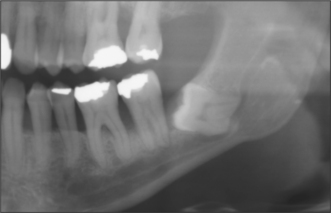

The radiographic examination of choice is a panoramic radiograph such as an OPT (Fig. 5.3), although periapical or oblique lateral views of the mandible may be taken as an alternative. When referring a case for treatment all recent relevant radiographs should be included to avoid further exposure to ionizing radiation.

image

Fig. 5.3 A mesioangular impacted lower third molar on the right and distoangular impaction on the left. (Note the unerupted third molars in the maxilla.)